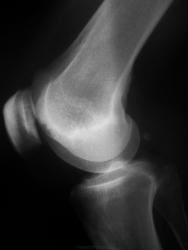

Пол пациента: Мужской пол Тип патологии: Другое Область исследования: Скелетно-мышечная система Методы исследования: Rg Мужчина 46 лет с клиникой ДОА. Как считаете, это Кенига или что-то иное? https://radiomed.ru/sites/default/files/styles/case_slider_image/public/user/2841/sdc10012.jpg?itok=qABNT0IF https://radiomed.ru/sites/default/files/styles/case_slider_image/public/user/2841/sdc10013.jpg?itok=BtAN6-yf https://radiomed.ru/sites/default/files/styles/case_slider_image/public/user/2841/sdc10014.jpg?itok=gjN2mPAt ID:9330 Ср, 24/11/2010 - 20:47 #1 DR.RAD Не на сайте Был на сайте: 12 лет 1 месяц назад Зарегистрирован: 25.03.2009 - 18:22 Публикации: 805 а артрит исключен? Ср, 24/11/2010 - 21:03 #2 sema Не на сайте Был на сайте: 10 лет 9 месяцев назад Зарегистрирован: 05.09.2010 - 08:39 Публикации: 233 О Кенега по моему можно думать в последнею очередь. Чт, 25/11/2010 - 00:29 #3 tatyana Не на сайте Был на сайте: 4 года 6 месяцев назад Зарегистрирован: 24.06.2009 - 08:33 Публикации: 2090 Внутрикостный ганглий (юкстаартикулярная киста кости) "самоуверенность дилетантов - предмет зависти профессионалов" Чт, 25/11/2010 - 00:52 #4 ЛГ Не на сайте Был на сайте: 9 лет 3 месяцев назад Зарегистрирован: 06.01.2010 - 12:31 Публикации: 3523 tatyana wrote: Внутрикостный ганглий (юкстаартикулярная киста кости) Спасибо, почитала - подходит! ------- Нет клиники артрита - ни температуры, ни гиперемии. https://www.youtube.com/channel/UCBGxoBUOqUT_bFhSeUgtWEw

Внутрикостный ганглий (юкстаартикулярная киста кости)

Нет клиники артрита - ни температуры, ни гиперемии.